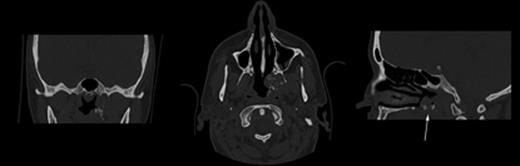

A left grommet was inserted and the lesion was biopsied, revealing an amyloid plaque confirmed on Congo Red staining. Computed tomography and magnetic resonance imaging scans were subsequently performed (see Figs 2 and 3) which showed a ‘1.5 × 2.3 cm mass arising from the torus tubaris and pterygoid fossa, protruding into the post nasal space’. Further radiological investigations of the entire body were conducted for investigation primary amyloidosis which all proved negative, confirming the diagnosis of primary isolated sinonasal amyloidosis. Management options were discussed and, due to the resolution of symptoms, a period of watchful waiting was commenced. Two years after initial presentation, the patient was discharged back to her GP without need for further intervention.